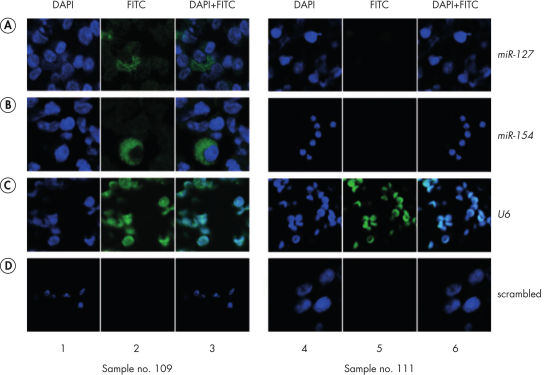

The miRCURY LNA miRNA Detection Control Probes are designed for use with our miRCURY LNA Detection Probes for both ISH and Northern blotting experiments. The control probes are similar in length and LNA design to the detection probes and therefore fall within the same Tm range. The U6 snRNA positive control and the scramble negative control can be used during optimization and troubleshooting of ISH experiments. In addition, these controls can be used to validate experimental results (see figure Detection of hsa-miR-127 and hsa-miR-154).See figures

In situ hybridization using double DIG- and double fluorescein (FAM)-labeled LNA probes in FFPE samples. Detection of hsa-miR-127 and hsa-miR-154 by fluorescent in situ hybridization using miRCURY LNA detection probes in cryopreserved bone marrow cells from an acute myeloid leukemia patient.

Detection of hsa-miR-127 and hsa-miR-154 by fluorescent in situ hybridization using miRCURY LNA detection probes in cryopreserved bone marrow cells from an acute myeloid leukemia patient.

Detection of hsa-miR-127 and hsa-miR-154 by fluorescent in situ hybridization using miRCURY LNA detection probes in cryopreserved bone marrow cells from an acute myeloid leukemia patient.

Panels A and B show the cytoplasmic detection of miR-127 and miR-154, respectively. Panel C shows the nuclear expression of the positive control U6 small RNA as visualized using the miRCURY LNA U6 control probe. No signal was detected when cells were hybridized with the miRCURY LNA scramble probe as a negative control, as seen in panel D. Data used with kind permission from Dr. Silvana Debernardi, Institute of Cancer, London, UK. Original figure appears in Dixon-McIver A, East P, Mein CA, Cazier J-B, Molloy G, et al. (2008) Distinctive Patterns of miRNA Expression Associated with Karyotype in Acute Myeloid Leukaemia. PLoS ONE 3(5): e2141. doi:10.1371/journal.pone.0002141.